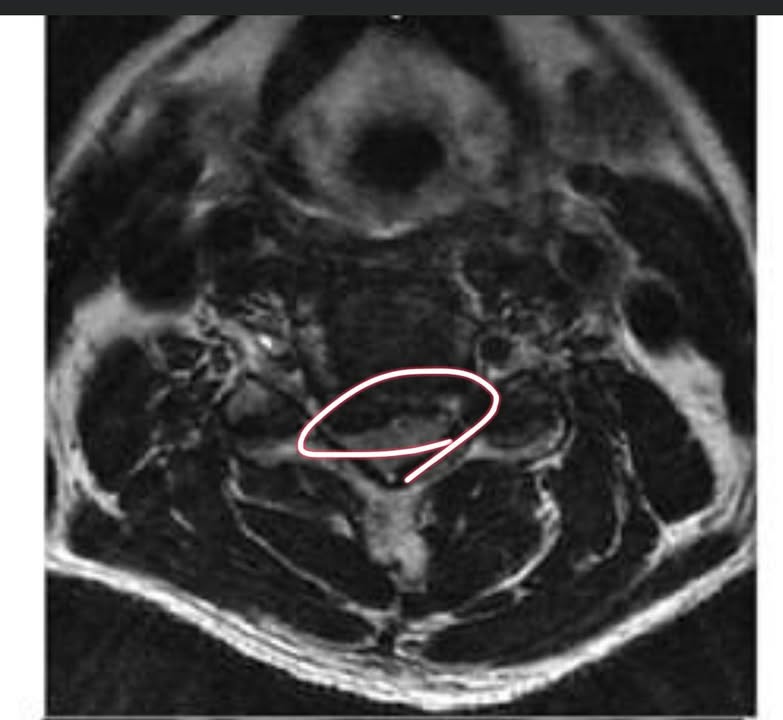

住在台北市的林伯伯,抱怨30幾年的頸椎痛,7年前復發,在台安醫院做MRI檢查,原本只是痠痛,來診前的一年已經嚴重麻跟刺痛,地區復健科診所做過針灸數個月,電療一年,熱療一年,拉脖子一年以上, 每天晚上固定疼痛超過一小時,最近發現對於冷熱水溫度感覺喪失才驚覺狀況不對,再拍一次MRI已經發現C4C5 脊髓病變。

診斷:C4C5中樞型脊髓型頸椎病

Cervical spondylotic myelopathy

評估:林伯伯雖然有脊髓壓迫,但是手腳還有力量,也沒大小便失禁,MRI也還沒嚴重脊髓變性跟水腫,所以決定嘗試跟林伯伯一起奮鬥治療,也明確告訴他壓迫到脊髓患者比較不好治療,如果治療兩週沒什麼特別進步,請他優先考慮大醫院接受頸椎人工椎間盤手術。